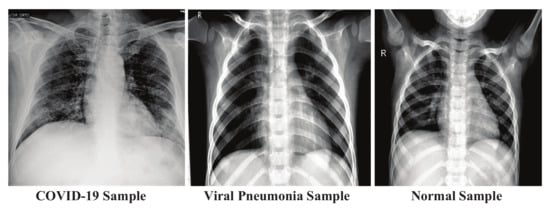

In this paper, the chest X-ray image datasets of COVID-19, viral pneumonia, and healthy cases are used for experiments. The dataset was collected from the chest X-ray dataset published by Kaggle. The whole dataset contains a total of 6863 X-ray images (JPEG) (1000 COVID-19 positive images, 3863 healthy images, and 2000 viral pneumonia images). The chest X-ray images dataset sample looks like Figure 3.

The collected datasets consist of the frontal view of hundreds of chest X-rays, and the scrutinized comprehensive public resource for COVID-19, viral pneumonia, and normal image data. The dataset is, manually, collected from various public source repositories into a DL-friendly format. The dataset consists of a small number of positive COVID-19 images, with respect to viral pneumonia and normal cases.

Figure 3. Dataset Sample.